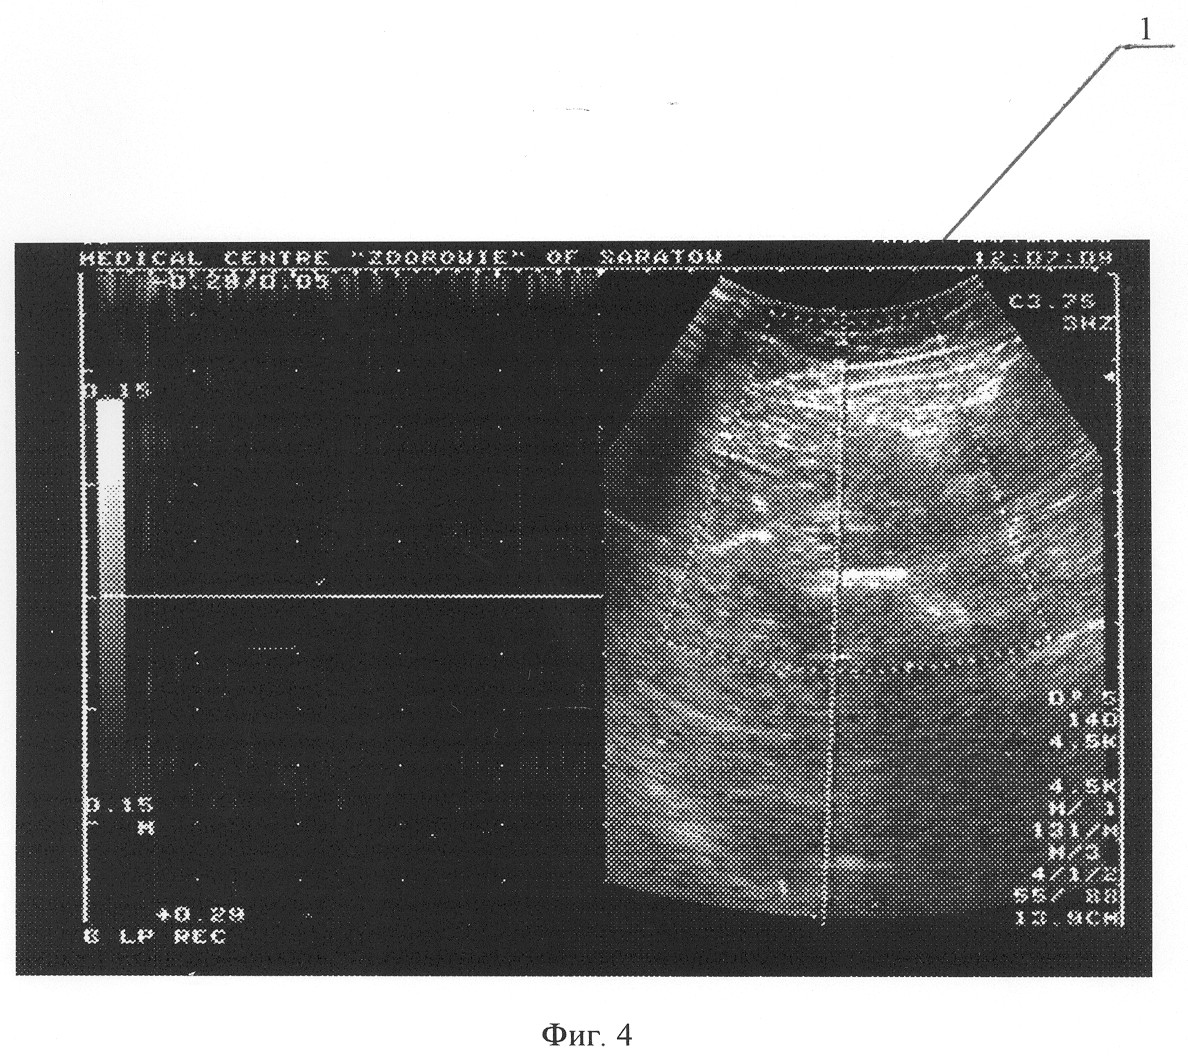

Пациент Б., 52 лет. При физикальном осмотре выявлено варикозное расширение большой подкожной вены и ее притоков на правой нижней конечности, положительный симптом Гаккенбруха на уровне правого сафено-феморального соустья. При дооперационном ультразвуковом дуплексном ангиосканировании в вертикальном положении выявлен патологический сафено-феморальный рефлюкс справа, в горизонтальном положении патологических венозных сбросов выявлено не было. Окончательный диагноз: Варикозная болезнь нижних конечностей. Частичная клапанная недостаточность большой подкожной вены справа. На фиг.1 и 2 представлены результаты ультразвукового дуплексного ангиосканирования большой подкожной вены в верхней трети бедра в ортостазе; на фиг.1 – во время проведения дистальной компрессионной пробы, на фиг.2 – во время выполнения пробы Вальсальвы, где 1 – просвет большой подкожной вены, 2 – антеградный кровоток по большой подкожной вене при компрессии икроножных мышц, 3 – ретроградный кровоток по большой подкожной вене при декомпрессии икроножных мышц, 4 – ретроградный кровоток по большой подкожной вене при выполнении пробы Вальсальвы.